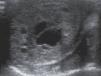

Recién nacido de 4 días de vida con ecografías prenatales normales que presenta desde el nacimiento aumento de tamaño y consistencia del testículo derecho (fig. 1). La ecografía (fig. 2) objetiva una tumoración testicular derecha (3×2×2,5cm) de ecoestructura mixta con áreas sólidas ecogénicas hipervascularizadas y múltiples espacios quísticos septados, sugestiva de teratoma maduro sin descartar otros tumores de origen embrionario. Se solicita estudio preoperatorio y marcadores tumorales: alfafetoproteína (AFP): 14.739ng/ml y beta-HCG<1,2 mUI/ml. Se procede a orquidectomía radical mediante abordaje inguinal, extirpándose una masa testicular de 3cm de diámetro, de consistencia dura, sin identificarse estructura testicular normal.